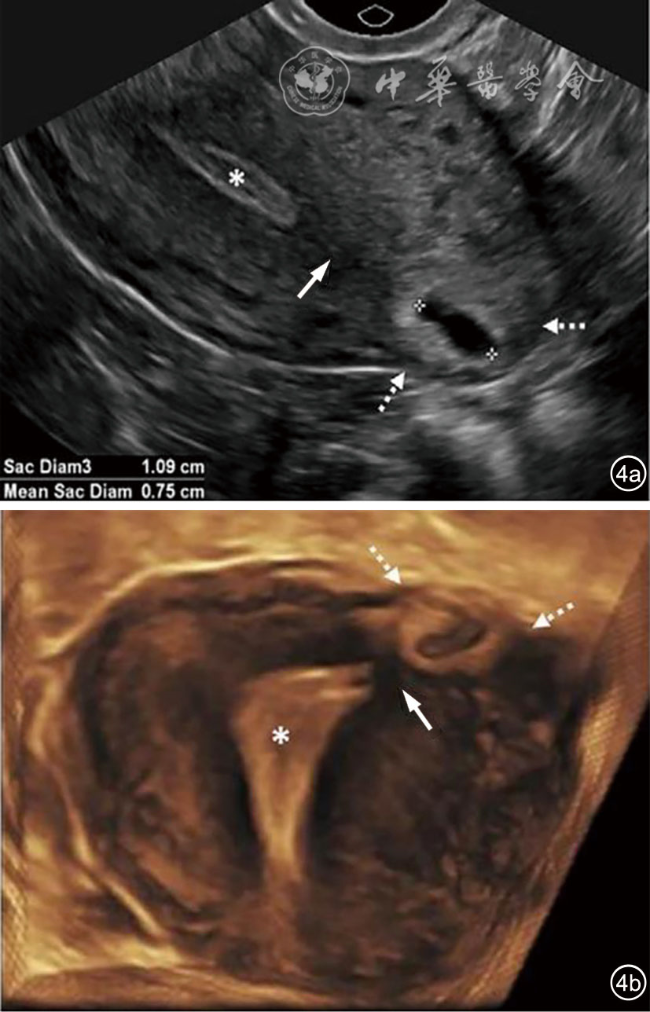

2.输卵管间质部异位妊娠:输卵管间质部异位妊娠较罕见,指受精卵着床于输卵管间质部(嵌入子宫肌壁内的输卵管近端部分)(图4)。超声诊断要点包括:(1)子宫与妊娠囊间滑动征阴性;(2)三维冠状切面重建图像显示子宫肌层部分包绕妊娠囊(妊娠囊周边子宫肌层组织呈“爪形征”),或子宫内膜与妊娠囊间可见薄层肌层组织;(3)间质线征仅偶见(图5),但该征象诊断输卵管间质部异位妊娠特异度较高。应避免使用‘宫角妊娠’或‘宫角异位妊娠’。

图4 输卵管间质部异位妊娠超声图像。图a为经阴道超声横切面灰阶图像,图b为三维超声冠状面重建图像。29岁孕妇(孕5周3天)的妊娠囊(测量游标)与子宫内膜(*)之间存在肌层组织(实线箭头),肌层组织的“爪形征”(虚线箭头)证实妊娠着床于输卵管间质部,提示为输卵管间质部异位妊娠。应避免使用‘宫角妊娠’或‘宫角异位妊娠’。三维超声冠状面重建可更清晰显示妊娠囊与子宫内膜分离,符合输卵管间质部异位妊娠(图4译自参考文献[1])